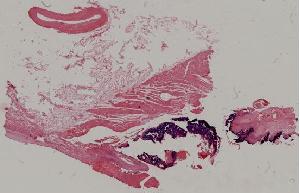

43.亚急性细菌性心内膜炎